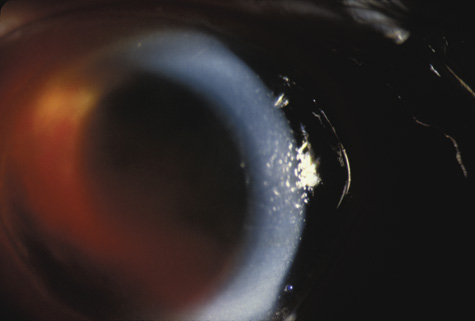

CORNEA

Abrasions of the corneal epithelium are common but because they heal rapidly, they are of little consequence. Endothelial damage can be more serious. A local concussion (coup effect) can rupture endothelial cells and loosen the intercellular tight junctions. They can also be damaged by being crushed against the iris and the lens. The transient corneal edema usually clears, but endothelial damage can be permanent. Follow-up studies of patients with traumatic hyphema show endothelial cell loss that correlates with the severity of the initial injury.28,29

When the cornea is abruptly forced backward by severe blunt trauma, it presses the iris against the lens, preventing the escape of aqueous into the posterior chamber. If enough force is applied, the entrapped aqueous dissects into the ciliary body, resulting in a recessed angle (Fig. 4). This tearing of the ciliary body is responsible for approximately 90% of the hyphemas seen after blunt trauma.31,32 Other causes of hemorrhage include separation of the iris from the ciliary body (iridodialysis) and sphincter tears. Ultrasound biomicroscopy can be useful in diagnosing dissection of the ciliary body or iridodialysis (Fig. 5).33–35